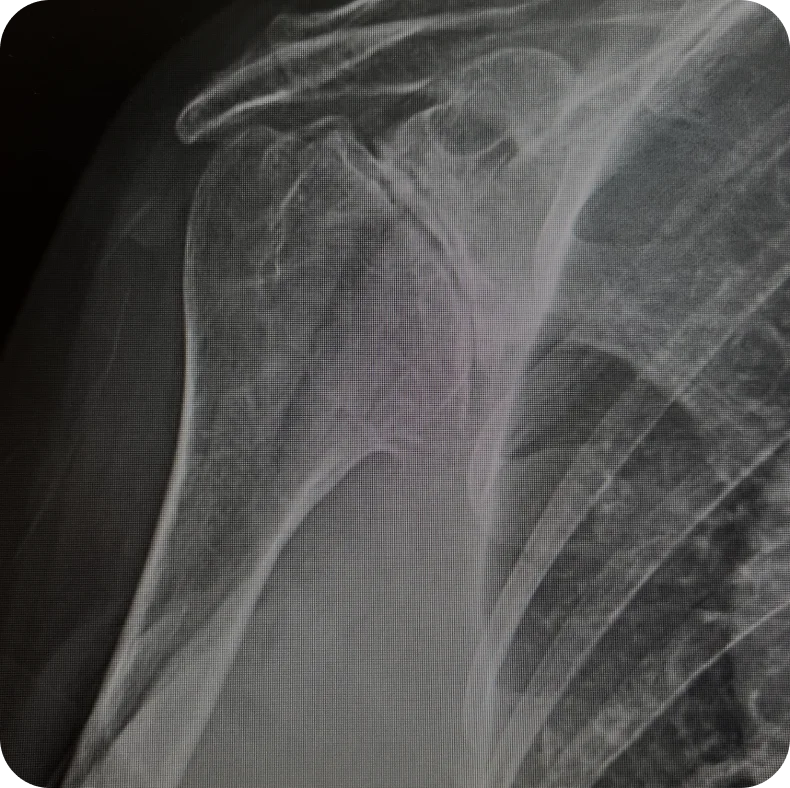

Arthritic Shoulder with a Rotator Cuff Tear

Arthritic Shoulder w/ a Rotator Cuff Tear

A reverse total shoulder replacement is designed for patients that have arthritis in the shoulder combined with a rotator cuff tear. Often, patients with complex fractures benefit from a reverse shoulder replacement. Dr. Drake’s goal is not only to eliminate pain but restore motion and get his patients back to normal activities.